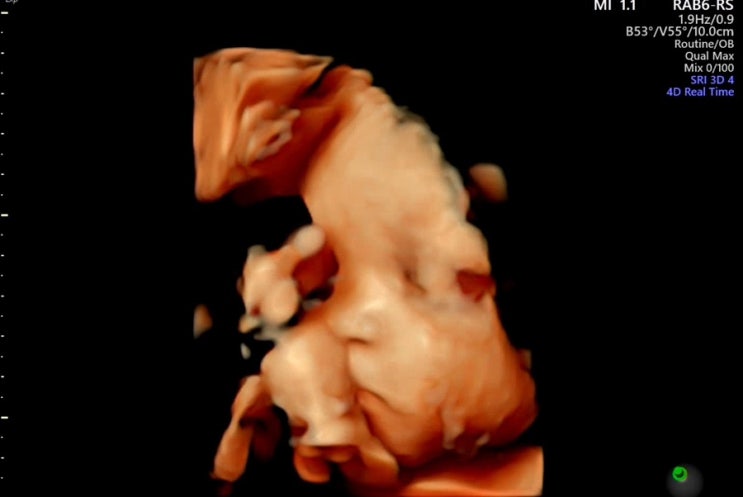

[임신일기 12] 임신 32주 증상 33주 정기검진

임신 32주차 되니까 배가 꽤 많이 무겁다! 조금 많이 걸으면 밤에 사타구니 아프고 많이 안 걸어도 기본적...